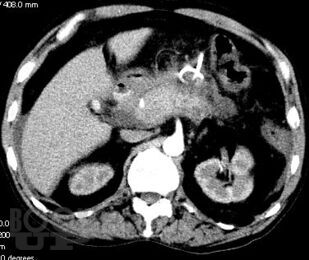

Острый панкреатит. Современные принципы диагностики и лечения

Учебно-методическое пособие посвящено актуальным проблемам этиологии, патогенеза, диагностики, современным методам консервативного и оперативного лечения острого панкреатита Представлены новые классификации, схемы консервативного лечения, современные виды оперативного лечения. Иллюстрировано рисунками, таблицами, имеются тестовые задания и задачи. Пособие предназначено для ординаторов и слушателей дополнительного профессионального образования, обучающихся по специальности 31.08.67 Хирургия.